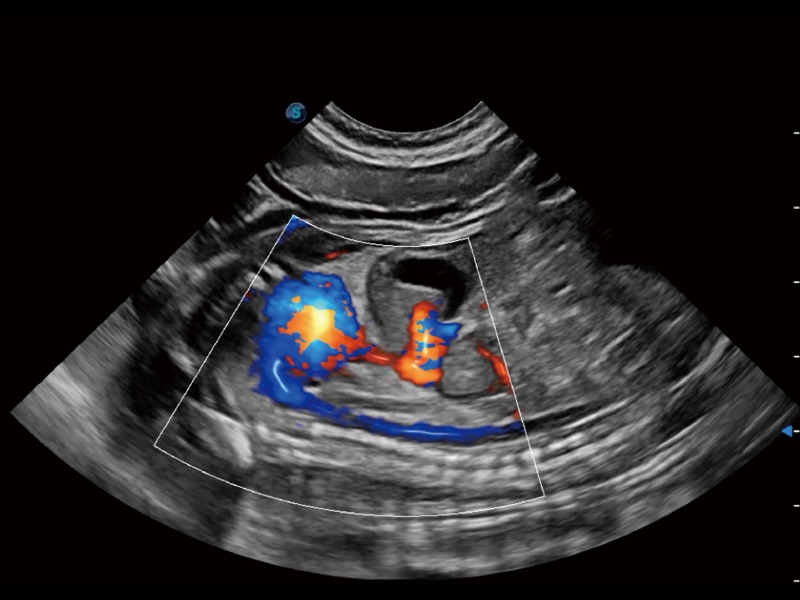

采用红、橙、黄、绿、青、蓝、紫这七种肉眼最为敏感的色彩,直观地显示组织内血流灌注的时间先后信息,更精准捕捉血流灌注走行细节。

能够基于左心室壁追踪和辛普森法,自动计算射血分数,支持多个可移动点描迹,与手动测量相比,极大节省了动物医生的时间和精力。

具备多种协议可选,同时支持17阶段划分法和专业的SE报告。